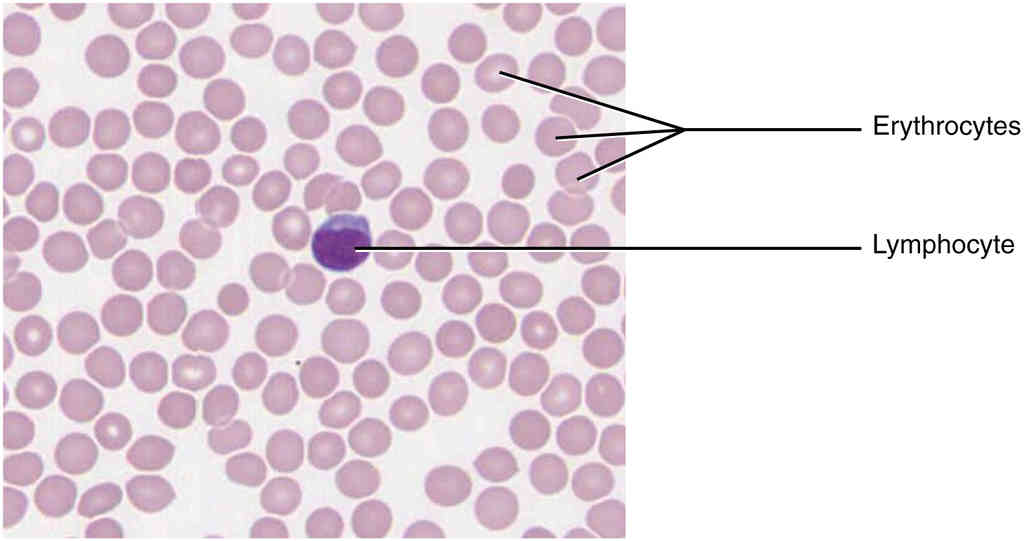

This page is under construction. For now, it is just a resource of the images found in the OpenStax Anatomy and Physiology Handbook. It wil slowly change into a revision tool. Each slide has a number. Use this to refer to the slide. When completed, it will have an unlabelled section, with labelled slides in parallel. On the unlabelled slides, write your answer and use the labelled slide to assess yourself. Keep track by also noting the number on each slide. Improvement at each attempt is important, more so than full marks on a first attempt.